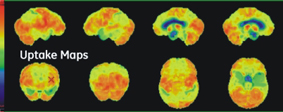

正子造影 (Positron Emission Tomography, PET) 是將去氧葡萄糖標幟上同位素氟-18 (18F-FDG),用以偵測人體內細胞代謝葡萄糖的情形。去氧葡萄糖是一種與自然葡萄糖相近的物質,安全性極高,不用擔心過敏或是其他身體不適症狀的發生。大腦新陳代謝十分旺盛,葡萄糖使用率極高;因此,可以利用此正子造影偵測腦部代謝的分布。若是出現不正常的區域,便意味著此處的腦細胞功能可能有變化。對於一些早期的腦部退化疾病如阿茲海默症,或是腦細胞局部功能異常的疾病,如癲癇;因為腦部尚未發生明顯的結構變化,上述的磁振造影還不一定能看到問題,這時正子造影就扮演非常重要的角色。

⊙ 案例:阿茲海默症患者在正子造影檢查上的表現

輕度患者

重度患者

▲圖示中紅色區域表示代謝率旺盛,藍色區域表示代謝率低下。我們可以看見臨床上症狀較為嚴重的患者,在正子檢查中明顯表現異常。